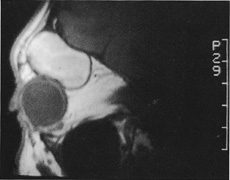

HISTORY AND PHYSICAL EXAMINATION A wide range of signs and symptoms may alert the ophthalmologist to involvement of the orbit by a pathologic process. These include proptosis or globe displacement; compressive optic neuropathy with visual field or visual acuity loss; refractive changes such as progressive hyperopia, restricted eye movements, and diplopia; optic disc changes, including pallor or edema; and fundus changes such as choroidal folds. These manifestations may be the consequences of a primary intraorbital disease or may occur secondary to involvement of the orbit by a process extending from the overlying soft tissues, periorbital sinuses, or intracranial cavity. All patients with suspected orbital pathology should have a thorough ophthalmic history and physical examination. Detailed questioning about the nature, onset, and progression of the chief complaint is necessary to formulate a differential diagnosis. Previous ocular and general medical history related to diseases, operations, medications, and family history should be obtained. A general review of systems will identify risk factors for related systemic diseases, such as hyperthyroidism, metastatic cancer, or lymphoma. A complete examination of the eye and periocular tissues is essential. Abnormal protrusion or displacement of the globe, extraocular motility disturbances, soft-tissue changes, and decreased corneal or periorbital cutaneous sensation should be specifically sought. Special attention always should be directed to evaluation of optic nerve function. Visual acuity testing alone is not sufficient because visual acuity often is preserved initially in patients with compressive optic neuropathy. All patients should be examined closely for detection of an afferent pupillary defect, abnormal color vision, or loss of contrast sensitivity. Formal perimetry should be performed to rule out peripheral field loss. If the presentation has been gradual, evaluation of old photographs may help establish the time course of the pathologic process. In selected cases, appropriate blood work to help identify orbital inflammatory or neoplastic processes also should be obtained. ORBITAL IMAGING Valuable information about the nature and extent of an orbital pathologic process is provided by imaging studies such as computed tomography (CT) scan, magnetic resonance imaging (MRI), and orbital echography. Better spatial resolution, ready accessibility, and lower cost make CT the preferred choice for orbital imaging in most cases. Orbital fat provides a natural contrast between most adjacent orbital structures on CT scanning, and orbital bones are visualized well. Computed tomography is essential for evaluation of the orbital bones because they cannot be imaged with MRI. Direct coronal or sagittal images are important to identify the relationship of a lesion to the optic nerve so that the surgical approach can be planned to avoid traversing the optic nerve (Fig. 1). Newer multislice helical CT scanners allow continuous acquisition of data so that a single rapid pass allows formatting in axial, coronal, and sagittal planes. Multislice CT provides shorter examination times with reduced motion artifact and radiation exposure when compared with conventional CT. Magnetic resonance imaging is useful in selected cases, especially when evaluating the orbital cranial junction. Significant bony artifact and a lack of orbital fat in the orbital apex make CT scan resolution of the orbital apex structures poor. Because cortical bone has low signal on MRI, there is no bone artifact when viewing the orbital apex on MRI. The lack of intervening fat in the apex to provide contrast is overcome on MRI because contrast is provided by the individual nuclear characteristics of each tissue so that the orbital apex structures are visualized well. Consequently, conditions that affect the optic nerve and chiasm, such as optic nerve meningioma and glioma, generally are evaluated with MRI rather than CT scan (Fig. 2). Use of a contrast agent such as gadolinium can further enhance the T1 signal intensity of lesions and is particularly helpful in imaging areas where there has been a breakdown in the blood–brain barrier. Because orbital fat produces a bright signal on T1-weighted images, orbital MR usually is performed with “fat suppression” to prevent masking of lesions. However, incomplete fat suppression can produce artifacts that may be misinterpreted as abnormal enhancement. A few other orbital conditions are better visualized with MRI than CT scanning.1–3 Often, organic foreign bodies, such as wood, are not imaged well with CT scan. These foreign bodies often are visible with MRI. However, care must be taken when imaging any metallic intraocular or intraorbital foreign body because the strong magnetic field of the MR scanner may cause the foreign body to shift position and damage surrounding structures. In some tumors and vascular anomalies, high blood flow is appreciated on MRI. This is caused by a lack of signal, known as a flow void, created by blood flowing rapidly through larger vessels. Tumors that originate in the brain and extend into the orbit secondarily, such as sphenoid wing meningioma, also are visualized well with MRI. However, bony detail and calcification within the meningioma are not imaged well. In unusual circumstances such as this, CT scan and MRI may prove to be complementary, and both techniques may be required to fully evaluate the orbital disease process. Orbital echography can provide useful information in the evaluation of orbital disorders. Because each tissue has its own acoustic characteristics, echography can provide a high degree of tissue contrast. Spatial resolution also is quite good. In some situations, echography can provide information not available on CT scan or MRI. These instances include detection and measurement of blood flow4 and intraoperative localization of small foreign bodies.5 Orbital echography requires specialized equipment and a large amount of expertise to obtain the detailed information that is readily available with CT scan or MRI; consequently, its use has decreased. Recent advances in orbital imaging have been summarized by Lee and colleagues.6 |